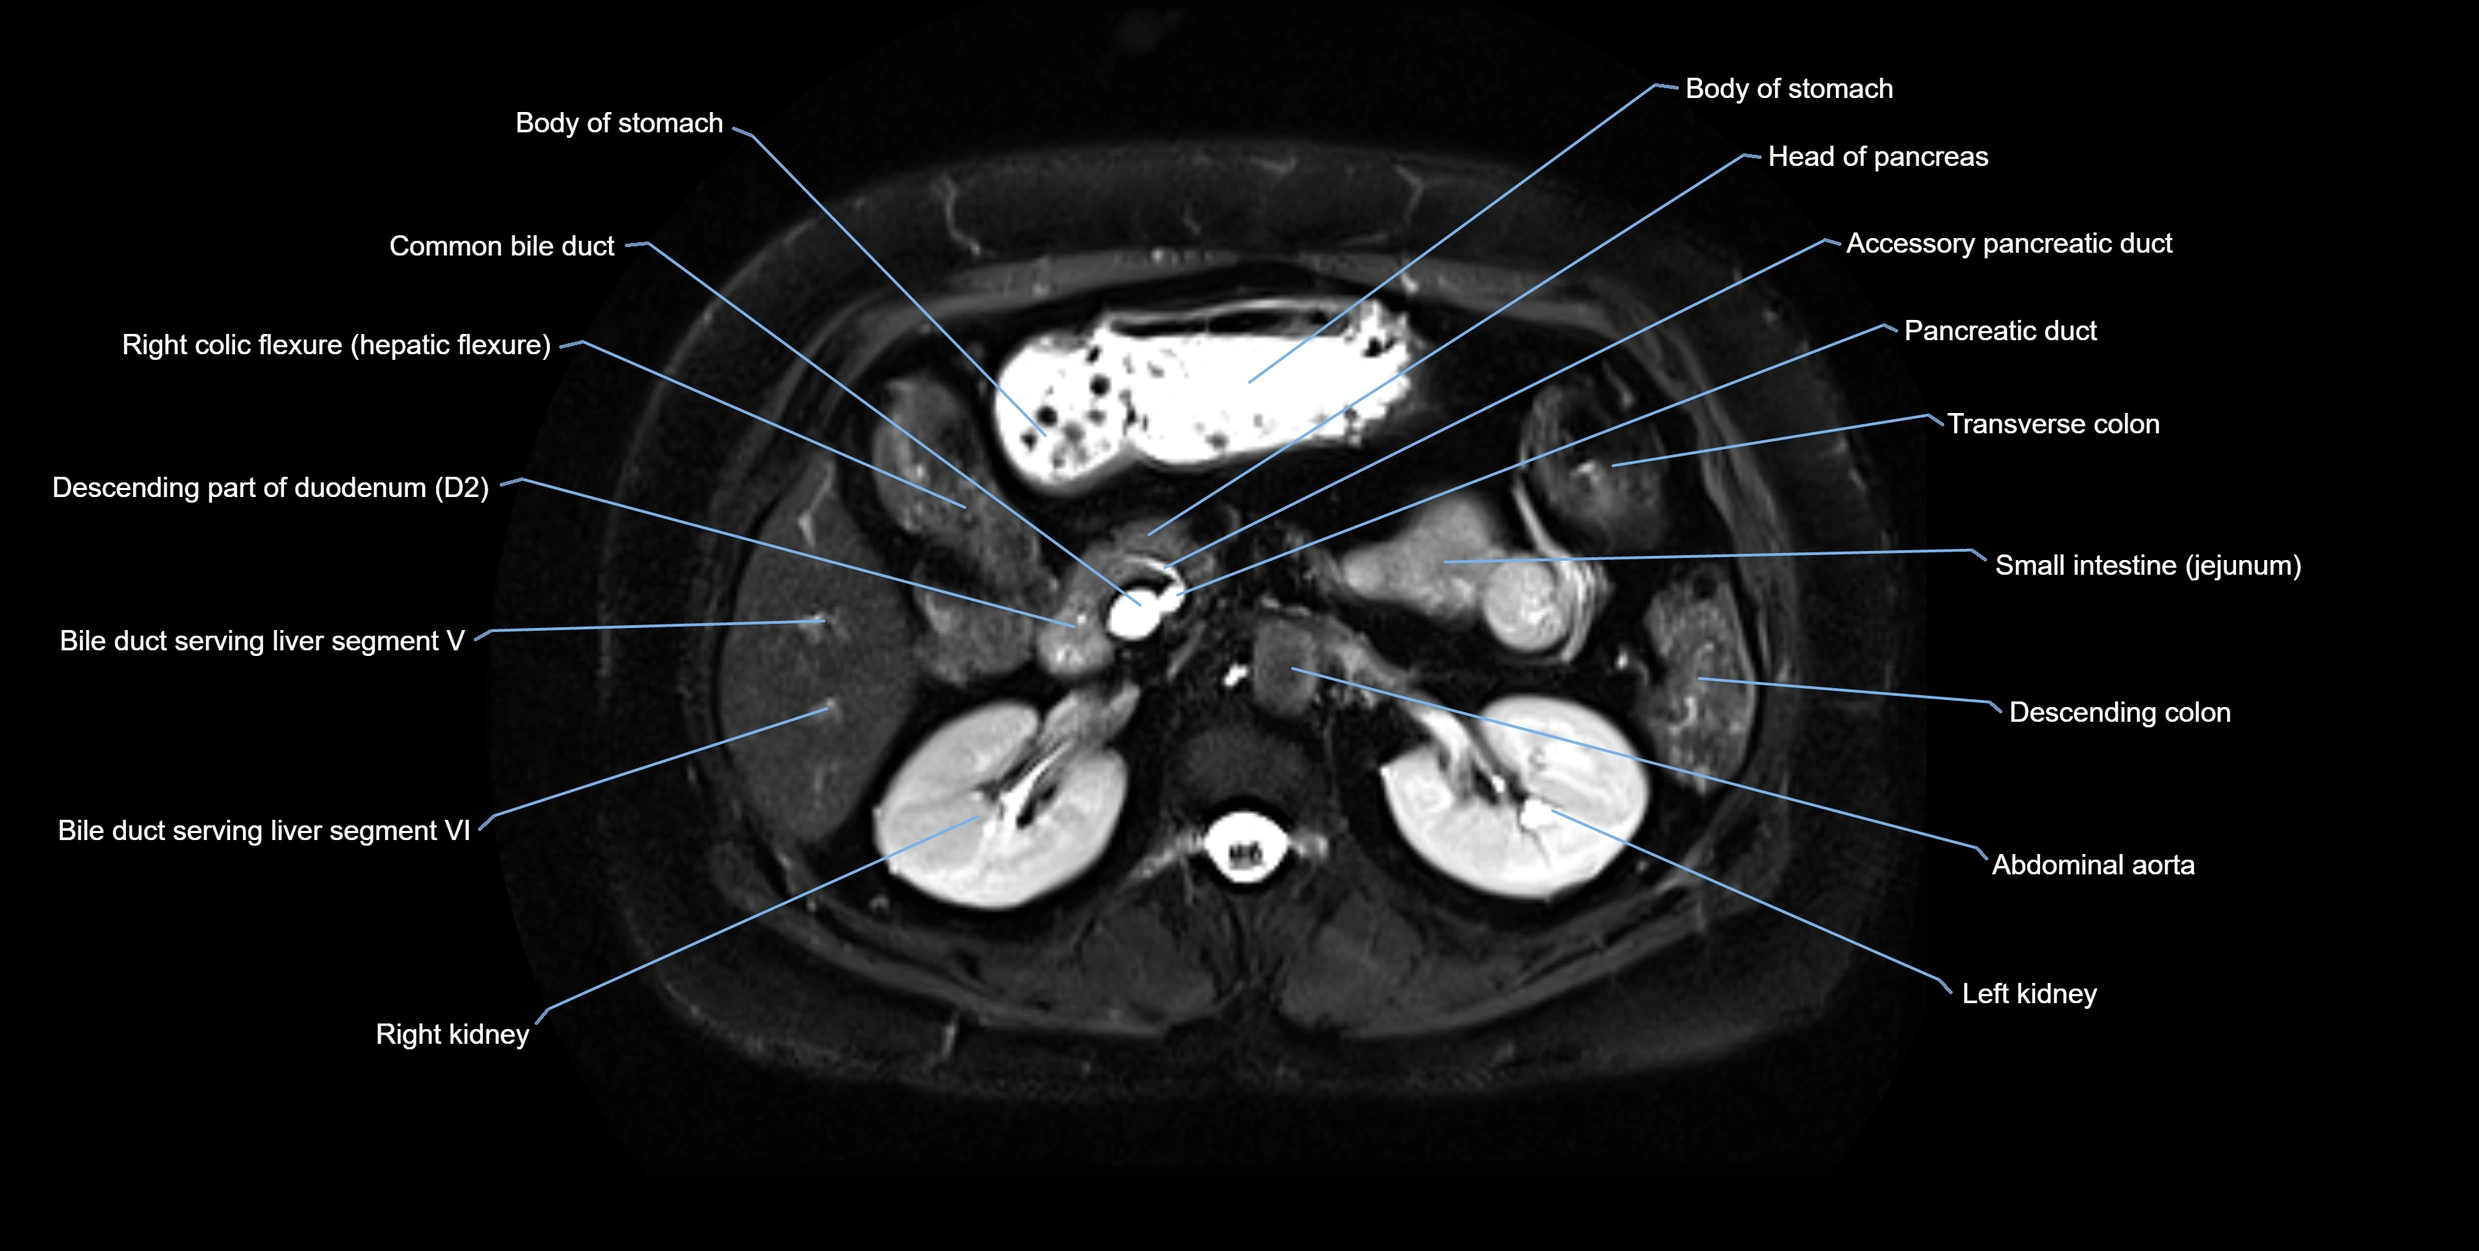

• Accessory duct: bright, thin linear structure in pancreatic head

• Stones, strictures, or air bubbles appear as dark filling defects

• Excellent for rapid evaluation of duct patency

MRI image

image